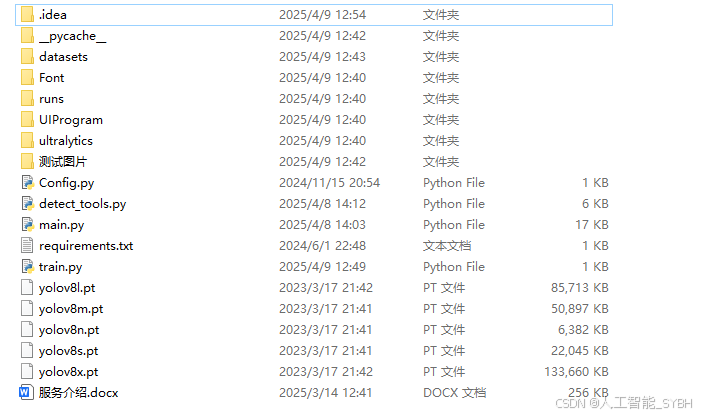

完整全部资源文件(包括测试图片、视频,py文件,训练数据集、训练代码、界面代码等),这里已打包上传至博主的面包多平台,见可参考博客与视频,已将所有涉及的文件同时打包到里面,点击即可运行,完整文件截图如下: